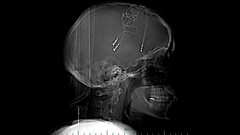

Brandy Ellis is a very different type of cyborg; having suffered from depression for years she opted to have electronics implanted in her brain to control her symptoms. Her feelings are literally regulated by a machine.